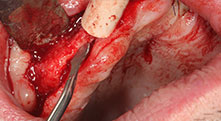

Бихте ли описали накратко, например, Вашия метод за мобилизиране на костни блокове за трансплантация?

Брату: Ние предпочитаме да събираме кост от външната страна на гребена в задната част на долната челюст. След разрязване на меките тъкани, ние използваме новите триони, за да определим количеството кост, което ще събираме. С този подход, ние използваме трионите за цялата препарация в почти 80% от случаите. Може да използваме и други пиезо инструменти и накрая длето за мобилизиране на блока. Ние смятаме, че това е изключително ефективна хирургична техника.

Можете ли да ни дадете няколко хирургични съвети и трикове от Вашата болница?

Брату: Ние предпочитаме да използваме техниката "сандвич" за аугментация в страничната долна челюст. Покритие на костта се подготвя с пиезо трион и кресталният фрагмент се фиксира с микровинтове. Поставяме смес от автогенна костна присадка и ксеногенен костозаместител между тях. Това работи много надеждно. Трябва винаги да осигурявате достатъчно оразмерени вертикални срезове при шиниране на алвеоларния гребен в долната челюст. В противен случай, костта лесно може да бъде счупена.